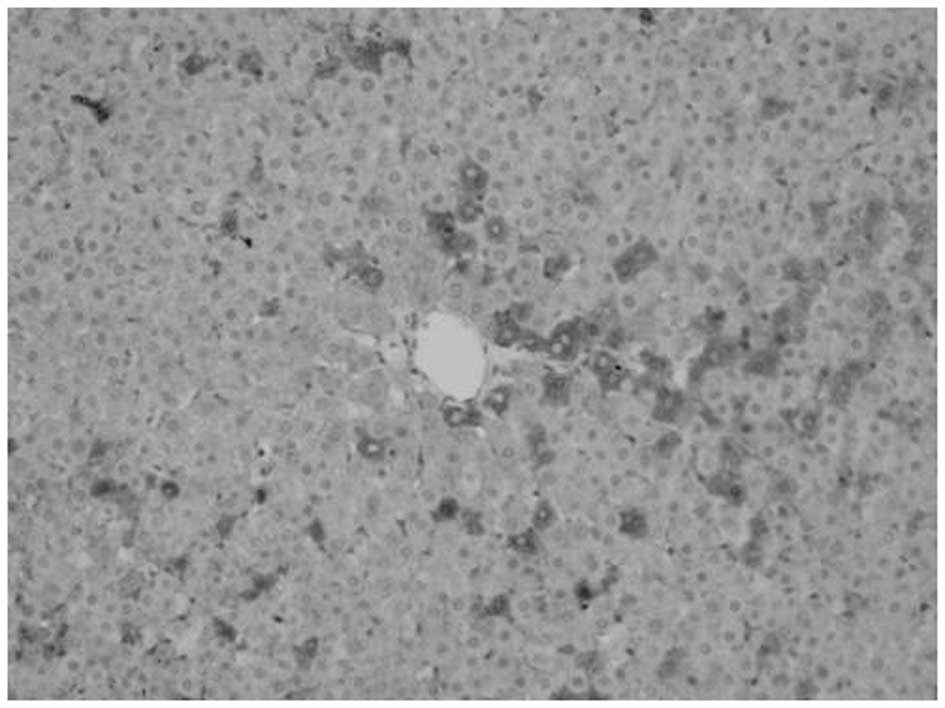

Proliferation of oval cells

Oval cells were found in the ductular area on day 1 following PH. Compared with mature hepatocytes, oval cells were observed to exhibit reduced volume, higher ratios of nucleus to cytoplasm, round- or oval-shaped nuclei and antibody OV6 expression. The number of oval cells increased with time. OV6-expressing cells were found to be distributed along the ductular to the parenchymal regions of the liver on days 3–7. Cell numbers peaked at day 7 and then decreased. A marked decrease was noted at day 14 following surgery, however, OV6-expressing cells were noted only in the ductular region. Compared with model, fewer OV6-expressing cells were identified in the matrine group (Figs. 2–5 and Table III).

Figure 5

Expression of OV6 in liver tissue of matrine group at day 14 following partial hepatectomy (magnification, ×200).